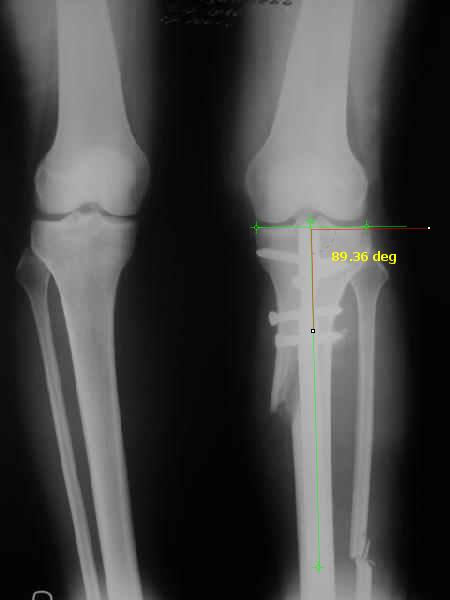

The analysis in the attached images is direct, just using the tools.

Tibial tilt is perhaps more than you want but the tibial correction is to 90 (very slight over

correction.

Will need full length views to tell us about the hka but it appears neutral.

Measurements took 4 mins